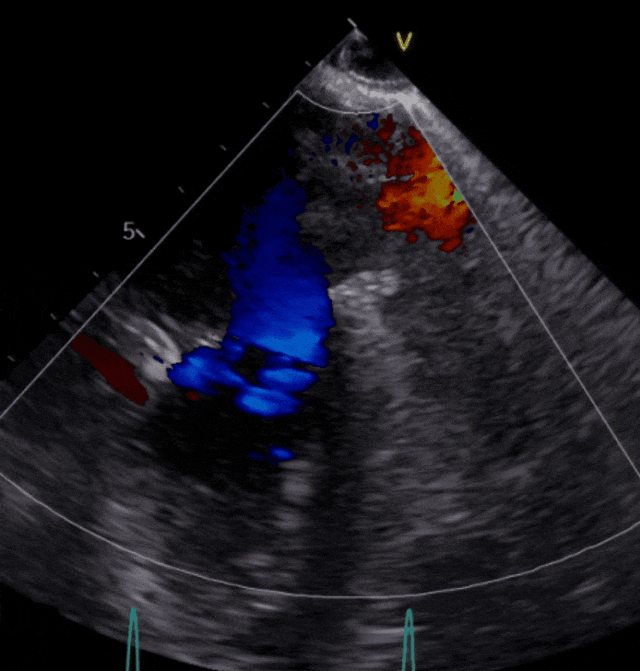

患者邵爷爷今年70岁,发现心脏瓣膜问题后辗转多地医院就诊未果,在昆山市中医医院经超声心动图检查,评估为二尖瓣重度反流。

图片

▲患者术前超声影像

患者二尖瓣3区前叶脱垂,脱垂宽度13mm,瓣口面积5.6cm2,平均跨瓣压差1.3mmHg。术前评估病人情况后决定采取策略在反流最大处植入一枚到两枚XTR或NTR,降低反流。